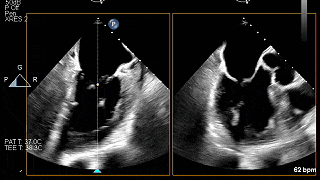

TEE

TEE-2D血流

夹合瓣叶后评估

释放夹合器前评估

夹合器释放后评估